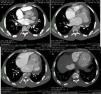

A 24-year-old black man presented to the emergency department of our hospital with fatigue and dyspnea at rest of two weeks duration. The transthoracic echocardiogram (Figure 1) revealed aneurysm of the right sinus of Valsalva (Figure 1A) dissecting into the interventricular septum (arrow) (Figure 1B), dilated left ventricle with moderately to severely impaired systolic function, and echocardiographic criteria for left ventricular non-compaction (Figure 1C and D). A submitral aneurysm and a dilated left atrium were also observed (Figure 1C). Doppler echocardiography showed mild mitral and aortic regurgitation. Multislice computed tomography with contrast (Figure 2) revealed an aneurysm of the right sinus of Valsalva (Figure 2A) dissecting into the interventricular septum (arrow) (Figure 2B), as well as a submitral aneurysm (Figure 2C) and non-compaction of the left ventricle (Figure 2D), confirming the echocardiographic findings. The patient was admitted to the cardiac intensive care unit of our hospital and treated with diuretics, angiotensin-converting enzyme inhibitors and digitalis, with dramatic improvement in symptoms. He was proposed for surgery but refused and was discharged in New York Heart Association class I. The patient died one year after the first admission.